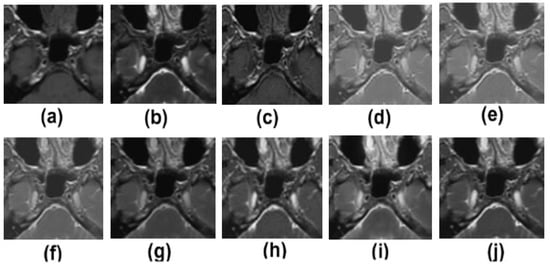

5. Experimental Results

5.2. Results and Discussion